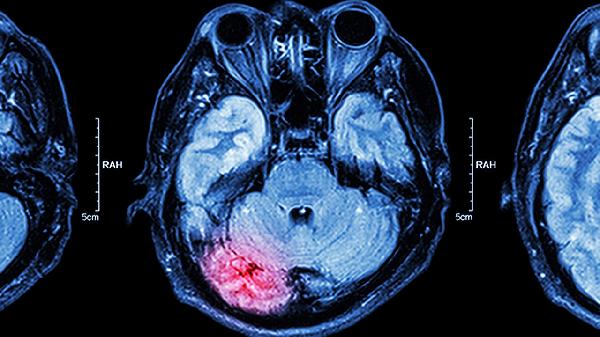

四、中风后遗症

可辅助改善中风后肢体麻木症状,其活血成分有助于促进侧支循环建立。严重偏瘫患者需配合康复训练,出血性脑卒中急性期禁用。用药期间监测凝血功能,避免与阿司匹林肠溶片联用。